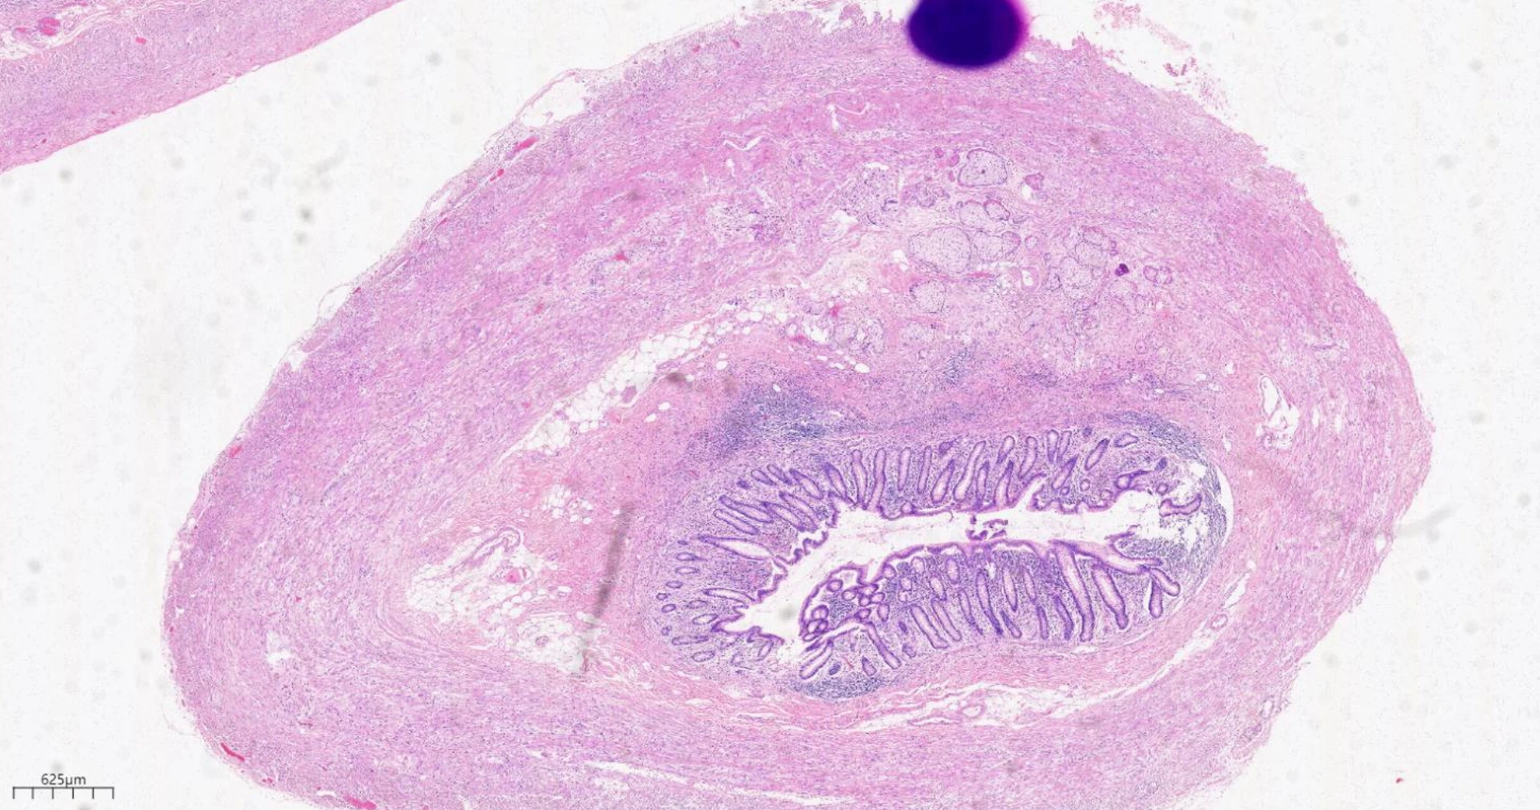

基于术中探查和术后病理,患者最终诊断:原发性盲肠管状腺癌合并阑尾杯状细胞腺癌,盲肠管状腺癌分期为T4aN0M0 II期IIC,阑尾杯状细胞腺癌分期为T4N0M0 II期IIB。

8IuhRsiHAtQkC3QT5rlx4I1i932ja5Cu.png

阑尾固有肌层杯状细胞癌